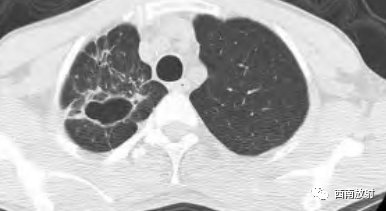

▲胞内分枝杆菌肺病,小叶中心结节(树芽征)

▲胞内分枝杆菌肺病,小叶中心结节(树芽征),双肺多发厚壁空洞。

▲胞内分枝杆菌肺病,右肺中叶支气管扩张,右肺下叶小叶中心结节